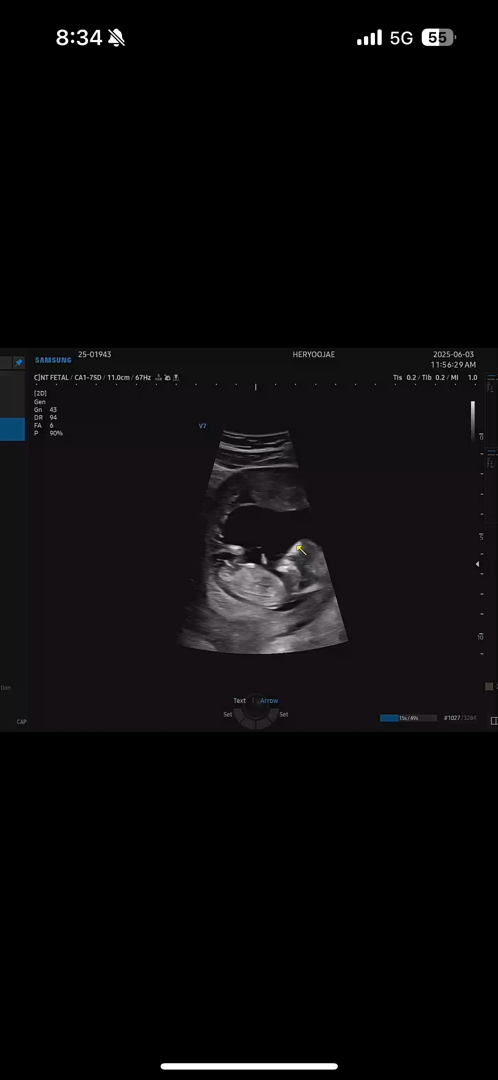

12주4일 각도법 고수님들 부탁드려요!

애매한데 딸각도 같아요. 좀더 기다려보세요.